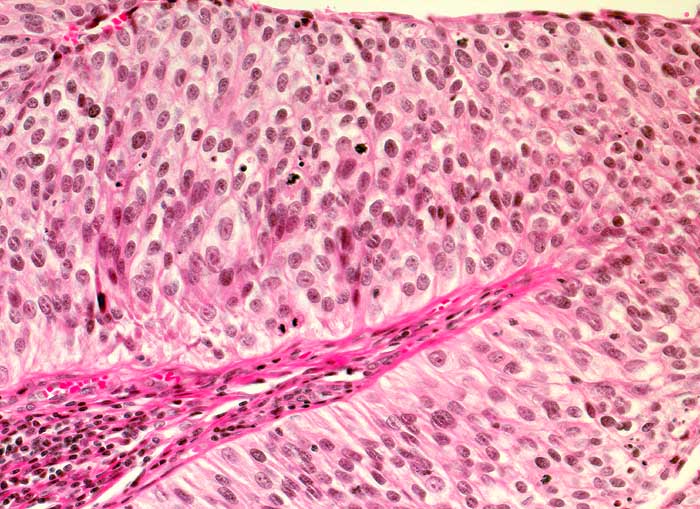

PathoPic – image database / PathoPic ID 6541 - Nicht invasives papilläres Urothelkarzinom, low grade pTa, G2

Nicht invasives papilläres Urothelkarzinom, low grade pTa, G2

Das bedeckende Urothel des papillären Tumors ist deutlich verdickt. Verglichen mit normalem Urothel sind die Zellen dieses mässig differenzierten Tumors leicht vergrössert, unregelmässig gelagert und hyperchromatisch. Gelegentlich sind Mitosen nachweisbar. Die Epithel-Stroma Grenze ist scharf.

Rezidivierende Urotheltumoren. Aktuell: Ureter-Tumor.